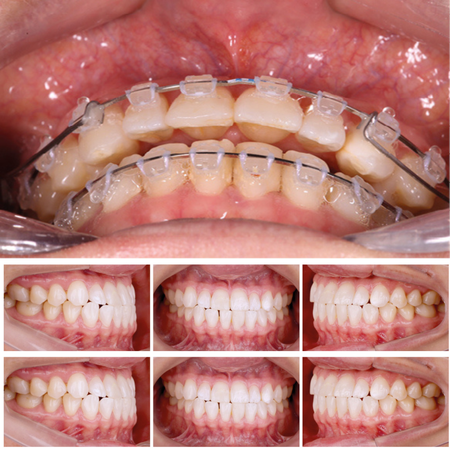

Otimizando os resultados dos alinhadores ortodônticos com mecânicas auxiliares: relatos de caso

INTRODUÇÃO: A terapia com alinhadores é uma abordagem ortodôntica amplamente utilizada. No entanto, realizar certos movimentos, como rotação e extrusão, continua sendo desafiador. Essa dificuldade é particularmente evidenciada em dentes com formas mais arredondadas, como caninos e pré-molares, e em casos de extrusão de incisivos. Isso muitas vezes resulta em precisão reduzida do tratamento. OBJETIVO: Este estudo teve como objetivo apresentar casos clínicos em que a mecânica...